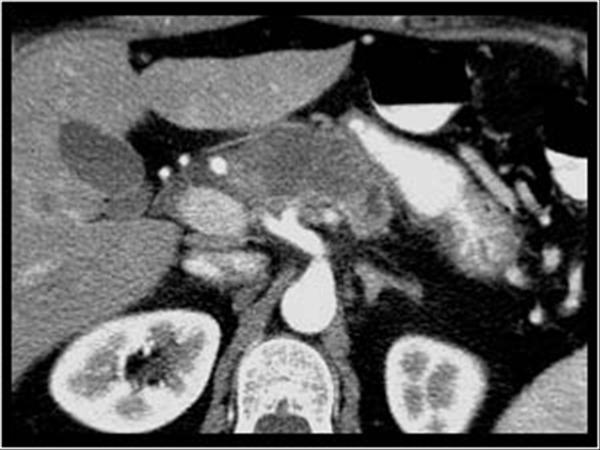

U tụy

» Thông tin: Nữ giới – 57 tuổi.

» Lâm sàng: Sút cân.